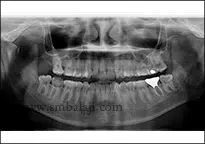

Under the guidance of Dr. S.M. Balaji, an experienced oral and maxillofacial surgeon, the patient’s journey to recovery began. Dr. Balaji carefully examined the patient’s condition, reviewing digital X-rays that revealed the fractured condyle. With a deep understanding of TMJ trauma, Dr. Balaji devised a surgical plan to stabilize the fractured bone segment and restore jaw function.